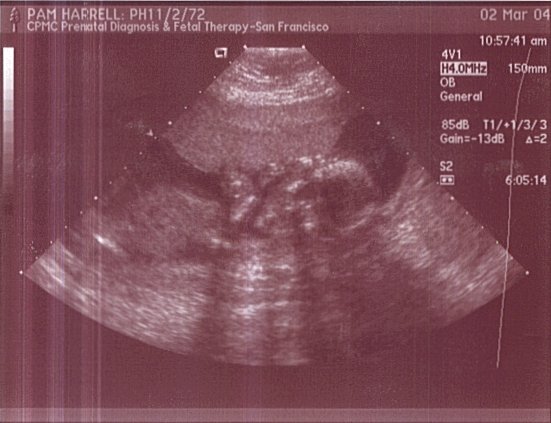

This is pretty much a full body shot from the front. A little difficult to distinguish, but limbs and head are visible. Her hands are lifted up to her face. This was taken on March 2, 2004.